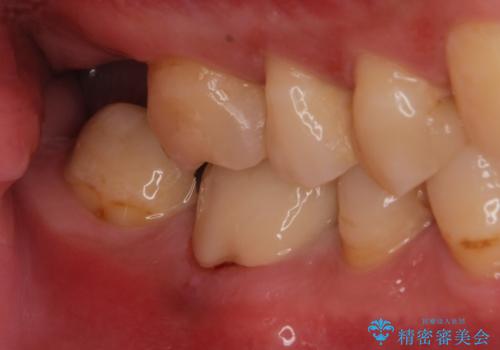

歯茎が腫れた。ジルコニアクラウンやりかえ。

- メンテナンスで来院された患者様です。

歯茎が腫れたとの事で歯の神経が失活していたので精密根管治療を行い、ジルコニアクラウンで治療を行いました。

神経が失活しているので痛みは感じにくいですがこのまま放置をしてしまうと骨が溶けたり痛みが出たりします。

このように歯茎にニキビみたいな物が出た場合、あるいは存在する場合すぐに歯科医院に相談することをおすすめします。